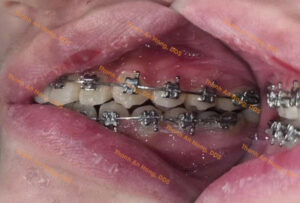

HÌNH ẢNH THỰC TẾ

Chỉnh khay dựng trục răng cối lớn hàm dưới